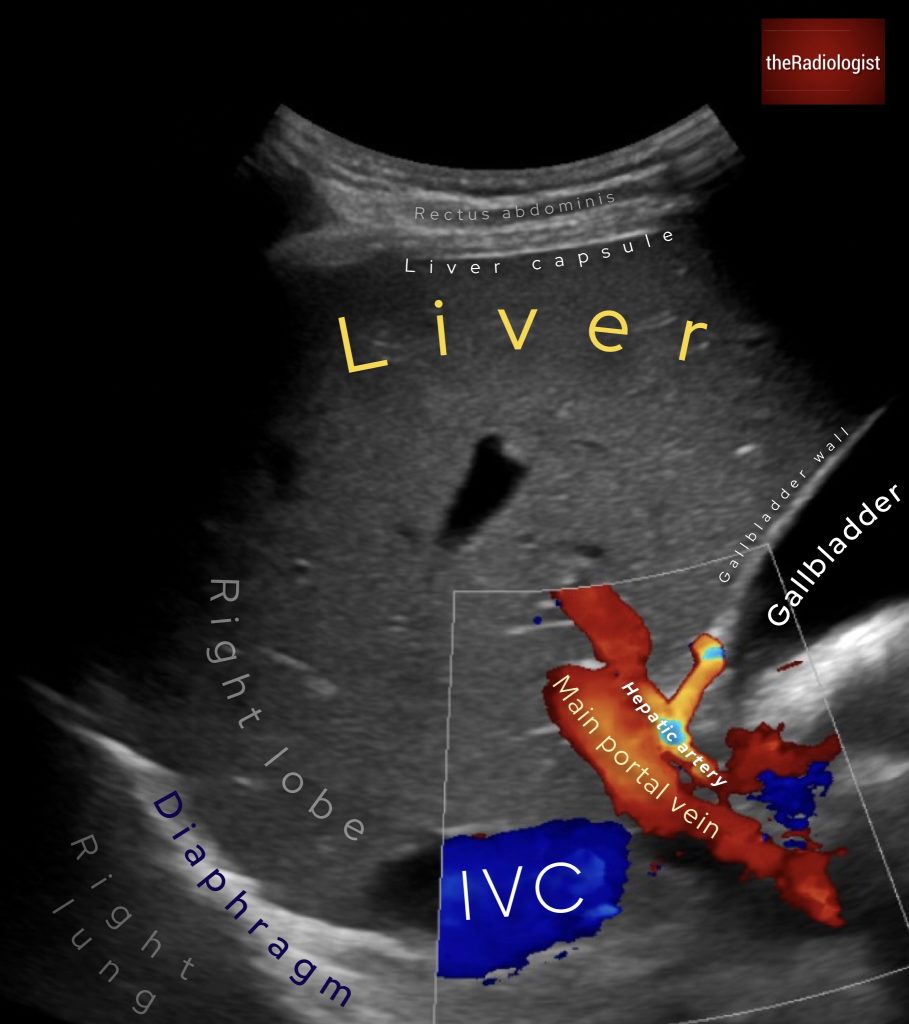

An abdominal ultrasound for this case. What is the arrow pointing at?

Choose one from the following: